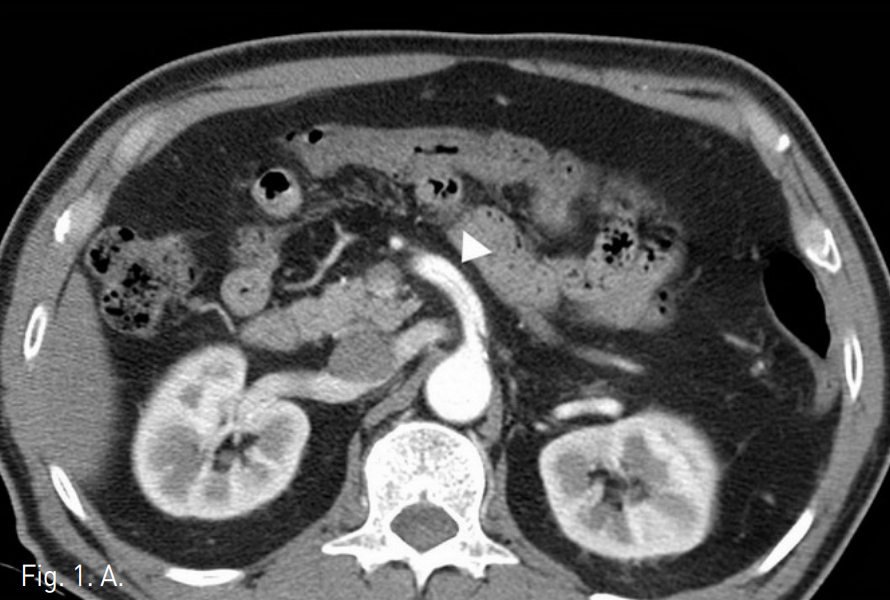

복부 CT에서 상장간막동맥(superior mesenteric artery, SMA)의 박리가 있었으며 중간결장동맥(middle colic artery)의 기시부가 경도로 좁아져 있고 가성 내강과 진성 내강의 혈류가 관찰되었다(Fig. 1). 같은 날 시행한 혈관조영술에서 상장간막동맥 기시부부터 회결장동맥(ileocolic artery) 분지부까지 침범한 동맥박리를 확인 하였다(Fig 2). 이 밖에 복강동맥과 하장간막동맥에는 특이 소견은 발견 되지 않았으나 변연 동맥 여러 곳이 동맥경화에 의한 좁아져 있었다. 소장과 대장의 동맥혈류가 유지되고 있어 스텐트삽입술은 시행하지 않았으며, 수축기 혈압 110mmHg, 심장박동 수 50~60회로 유지하며 보존적 약물치료를 하였다. 환자의 복통은 진정되었으며 7일 후 퇴원하였다. 5개월 후 추적검사로 시행한 복부 CT에서 상장간막동맥의 박리피판이 여전히 관찰되며 진성 내강과 가성 내강의 개통성을 확인할 수 있었고 기타 변연 동맥의 폐색은 없는 것이 확인되었다. 하지만 1년 추적 복부 CT에서는 가성 내강을 따라 혈전이 형성되었고(Fig. 3) 원위부로 혈관 폐색의 소견은 보이지 않았으며 장관의 허혈이나 경색 소견 또한 관찰되지 않았다. 2년 추적 CT에서 상장간막동맥은 정상화되었으며 박리나 동맥류 소견은 관찰되지 않았다.

Fig. 1

A, B. (A) The first abdominal CT angiogram taken in ER. The axial image shows dissection in the proximal part of SMA (arrowhed). Both true and false lumens were patent. (B Mild narrowing at the orifice of the middle colic artery is seen (arrow).